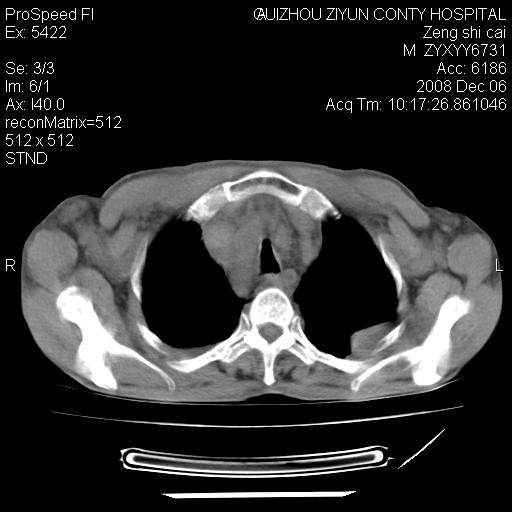

标题: CT16961:M、71岁,咳嗽半年,无血痰;胸片示右肺占位。 [打印本页]

标题: CT16961:M、71岁,咳嗽半年,无血痰;胸片示右肺占位。

右肺癌并纵隔淋巴结及胸膜转移可能性大

右肺癌并纵隔淋巴结及胸膜转移。建议气管镜

右肺纵隔型肺癌伴纵隔淋巴结及胸膜转移!

右肺纵隔型肺癌伴纵隔淋巴结转移!双侧胸水!

1)考虑右肺上叶纵隔型肺癌伴纵隔淋巴结转移。2)心包积液,双侧胸腔积液。

右肺癌并纵隔淋巴转移,腹膜后转移可能性大,两侧胸腔积液

右肺癌并纵隔淋巴结及胸膜心包转移,好多团团点点,看得有点想吐

右肺上叶纵隔型肺癌伴纵隔淋巴结转移。心包积液,双侧胸腔积液。

右上肺癌并纵隔淋巴结及胸膜转移。

右肺纵隔型肺癌伴纵隔淋巴结转移!双侧胸水\\心包积液

建议强化!主要鉴别是淋巴瘤与肺癌淋巴结转移。

右肺纵隔型肺癌伴纵隔淋巴结及胸膜转移